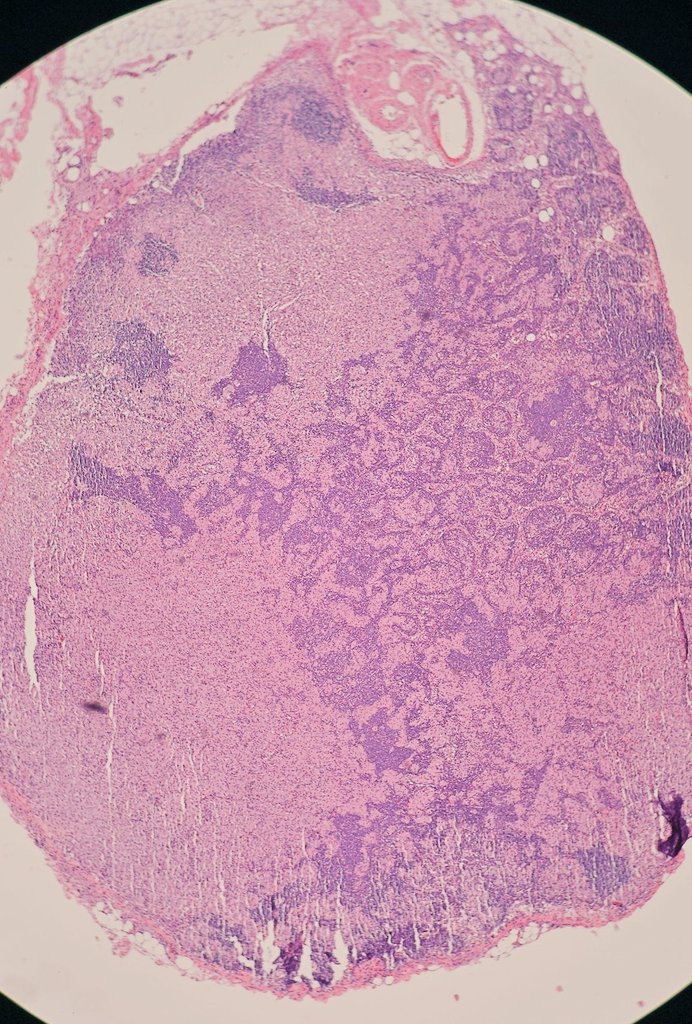

Young female with untreated HIV presents with GI bleeding and adenopathy. Which stain or stains would be the most useful to determine the cause of her symptoms? Pictures: Colon Bx, Mesenteric lymph node, Omentum #GIpath #pathology